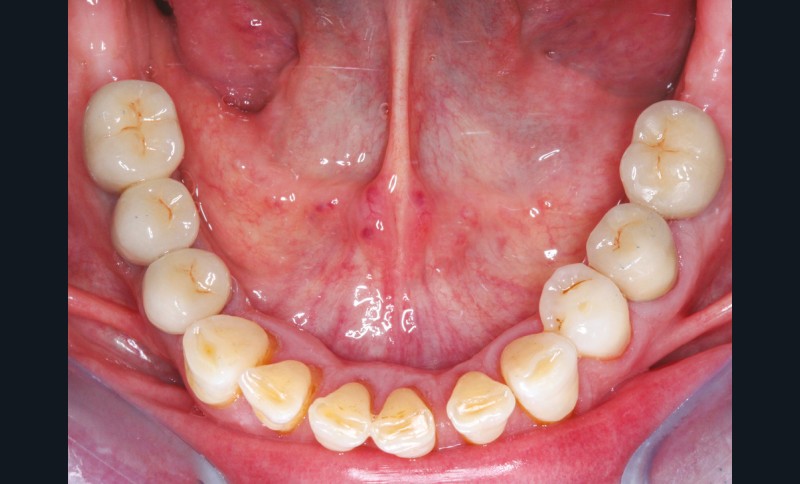

La perte d’une ou plusieurs dents entraîne la perte des points de contact, responsables de la stabilité et de la continuité de l’arcade. Par conséquent, une avulsion a pour première conséquence la migration ou la version d’une ou plusieurs dents distales (fig. 1 et 2). Cela est vrai en antérieur comme en postérieur.

Cette version, quand elle se produit, modifie les espaces interdentaires et complique l’hygiène proximale des patients. Des caries peuvent alors se développer en interproximal sans que cela soit forcément visible à l’examen visuel (fig. 3 et 4). Les radios de type bite-wing (rétro-coronaires) prennent alors tout leur sens (fig. 5 et 6).

La version des dents distales peut aussi avoir des conséquences parodontales désastreuses : sur un parodonte réduit, une hypermobilité peut se développer, une poche parodontale peut aussi apparaître. Chez un patient parodontal, un « effet domino » est possible, des extractions non compensées diminueront donc le pronostic des dents restantes (fig. 7 à 9).

Le principe de protection mutuelle implique que les dents postérieures protègent les antérieures lors de la mastication. Des extractions non compensées de molaires, par exemple, entraîneront une hypersollicitation des antérieures et une usure importante du fait du principe de calage ainsi qu’un risque de perte de dimension verticale (fig. 10 à 13).

La répartition de la charge occlusale sur l’ensemble d’une arcade est aussi perturbée après une ou plusieurs extractions, ce qui peut occasionner des surcharges occlusales pour les dents restantes. Selon le délabrement coronaire de la dent [10], une fracture coronaire amélo-dentinaire ou corono-radiculaire peut intervenir sous cette surcharge occlusale et engager le pronostic de la dent concernée (fig. 14 à 17).